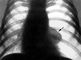

Основным рентгенологическим признаком пневмоторакса является участок просветления, лишенный легочного рисунка, расположенный по периферии легочного поля и отделенный от спавшегося легкого четкой границей, соответствующей изображению висцеральной плевры (рис. 1). При рентгенологическом исследовании можно выявить связь плевральной полости с внешней средой. Открытый пневмоторакс на вдохе характеризуется увеличением газового пузыря, дальнейшим спадением легкого, смещением органов средостения в здоровую сторону, а купола диафрагмы — книзу. При закрытом пневмотораксе рентгенологическая картина зависит главным образом от количества воздуха, скопившегося в плевральной полости, и связанного с этим внутриплеврального давления. Если давление ниже атмосферного, количество воздуха в плевральной полости невелико и легкое коллабировано незначительно, на вдохе оно увеличивается в объеме, на выдохе — спадается. При давлении выше атмосферного легкое резко коллабировано, его дыхательные экскурсии едва заметны, органы средостения смещены в здоровую сторону, диафрагма — книзу. Если давление в плевральной полости равно атмосферному, легкое коллабировано частично, дыхательные экскурсии сохранены, средостение смещено незначительно.